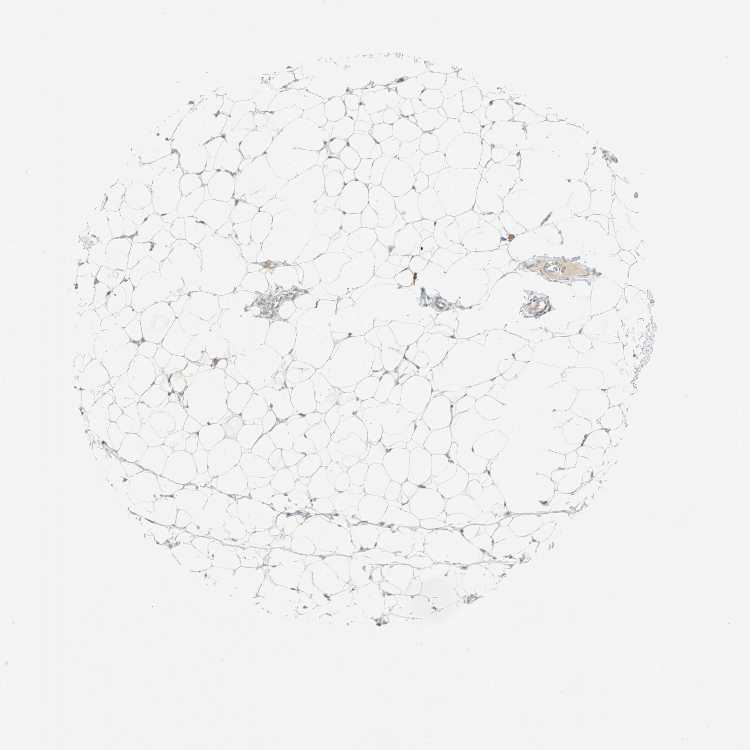

SOFT TISSUE 1 - Antibody stainingi

Antibody staining in the annotated cell types in the current human tissue is reported as not detected, low, medium, or high, based on conventional immunohistochemistry profiling in selected tissues. This score is based on the combination of the staining intensity and fraction of stained cells.

Each image is clickable and will lead to virtual microscopy that enables deeper exploration of all samples and also displays staining intensity scores, fraction scores and subcellular localization as well as patient and tissue information for each sample.

Antibody HPA005697

Fibroblasts Not detected

SOFT TISSUE 2 - Antibody stainingi

Peripheral nerve Not detected